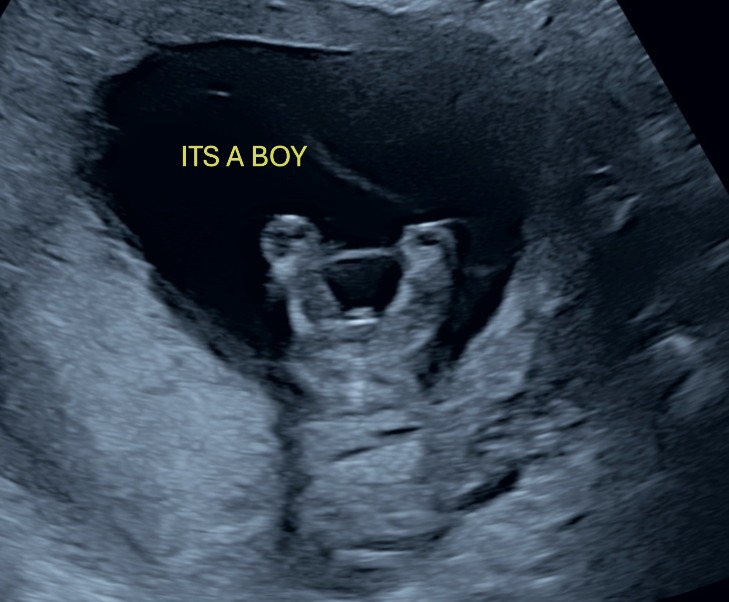

Wil je weten of je een jongen of een meisje kunt verwelkomen, dat kan! De geslachtsbepaling kun je bij ons vanaf 13+2 weken zwangerschap inplannen, je kunt het dan met ongeveer 98% zeker weten. Heb je net een weekje meer geduld, vanaf 14+5 weken is het bepalen van het geslacht voor 99,9% zeker.

Elk kind ontwikkelt zich anders, en soms is het ongeacht het aantal weken nog net iets te vroeg om te zeggen of het een jongen of een meisje is.

Vroege 2D geslachtsbepaling

Vanaf 13+2 weken tot 14+2 weken 10-15 min, inclusief 2 zwart/wit foto afgedrukt. We zijn expert in het uitvoeren van deze vroege geslacht echo, door oa. onze ervaring en de goede gedetailleerde echo machine. We kunnen het geslacht direct met je delen we kleuren dan de hele kamer roze of blauw, maar we kunnen natuurlijk ook het geslacht op een briefje zetten zodat je het later zelf kunt bekijken of kunt doorgeven voor een gender reveal feestje. Wij kunnen het ook voor je doorbellen/mailen. Naast het beoordelen van het geslacht blijft er genoeg tijd over om samen naar jullie kleintje te kijken!

Standaard 2D geslachtsbepaling

Vanaf 14 weken 10 -15 min, inclusief 2 zwart/wit foto’s afgedrukt, we kunnen het geslacht direct met je delen we kleuren dan de hele kamer roze of blauw, maar we kunnen natuurlijk ook het geslacht op een briefje zetten zodat je het later zelf kunt bekijken of kunt doorgeven voor een gender reveal feestje. Wij kunnen het ook voor je doorbellen/mailen. Naast het beoordelen van het geslacht blijft er genoeg tijd over om samen naar jullie kleintje te kijken!